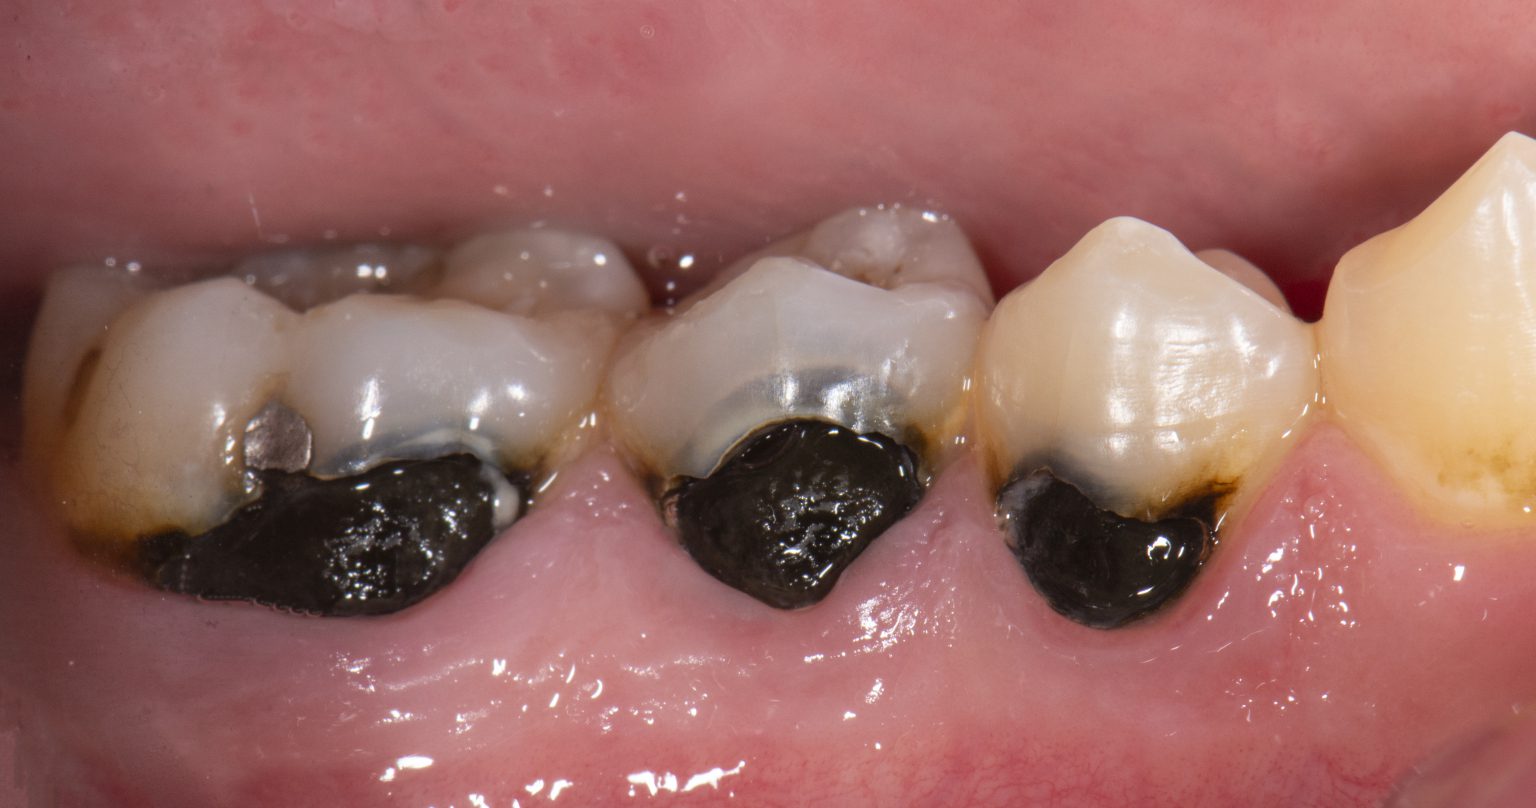

Why Does Silver Diamine Fluoride Turn Teeth Black . Get a detailed overview of silver diamine fluoride, including the benefits of silver diamine fluoride treatment, how it can improve. Silver diamine fluoride (sdf) is a liquid substance used to help prevent tooth cavities (or. Cavities are often soft and brown in color. Sdf treatment hardens the cavities and turns the area black (which shows that the sdf is working). All decayed areas will permanently stain black within a week of treatment, although healthy tooth structure will not stain. What are the risks related to silver diamine fluoride? After sdf is put on children’s teeth, the decayed spots will turn black and stay black (see photo). Sdf currently has fda clearance for treating tooth sensitivity. It may take up to a week for the. If sdf comes into contact with skin, it will cause a small. The main side effect is that any porous tooth structure (caries or hypomineralization), will stain black. What is silver diamine fluoride? The potential benefits of sdf treatment for caries arrest include its low.

The potential benefits of sdf treatment for caries arrest include its low. Cavities are often soft and brown in color. Sdf currently has fda clearance for treating tooth sensitivity. Sdf treatment hardens the cavities and turns the area black (which shows that the sdf is working). Get a detailed overview of silver diamine fluoride, including the benefits of silver diamine fluoride treatment, how it can improve. What is silver diamine fluoride? If sdf comes into contact with skin, it will cause a small. All decayed areas will permanently stain black within a week of treatment, although healthy tooth structure will not stain. After sdf is put on children’s teeth, the decayed spots will turn black and stay black (see photo). It may take up to a week for the.